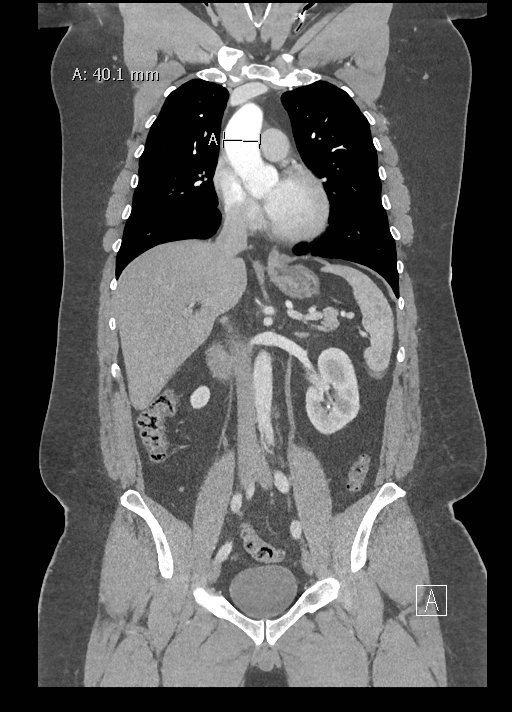

Point-of-care cardiac echocardiogram demonstrated a dilated ascending aorta (illustrated in red) measuring approximately 4 cm in the parasternal long axis (PLAX). A dilated aortic arch (illustrated in green) also measuring approximately 4 cm was appreciated using the suprasternal notch view (SSNV). A follow-up computed tomography angiogram (CTA) was performed, validating bedside ultrasound measurements.

The diagnostic criteria for dilated thoracic aneurysm is based on multiple factors including age, sex, and body size.2 An aortic root diameter of ³ 4.0 cm constitutes an ascending aortic dilation.3,4 Point-of-care cardiac and SSNV ultrasound of the thoracic aorta has been validated as an accurate study when performed by emergency physicians to identify thoracic aortic aneurysms (sensitivity of 71.4%, specificity of 100% when compared to gold standard of CTA). 5 This case is an example of the utility of rapid bedside diagnostic ultrasound, specifically the SSNV, in assessment of thoracic aneurysms.